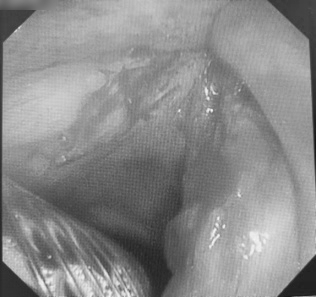

在充分评估支气管镜检查风险后,医生在局麻下为老者实施了电子支气管镜检查:右侧声带前中 1/3 可见肿瘤组织致喉狭窄。术后行活检组织病理证实为「高分化鳞癌」。